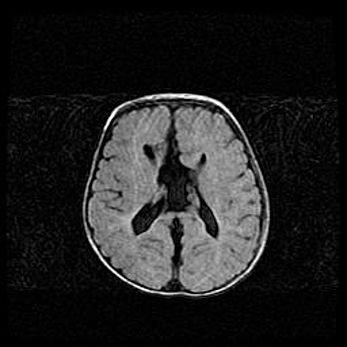

Церебральная ишемия II.

Возраст: 5 дней

Вес: 3400 г

Пол: женский

Окружность головы: 35 см

Срок гестации: 39 недель

Церебральная ишемия – это заболевание, характеризующееся недостаточностью (гипоксией) либо полным прекращением (аноксией) снабжения мозга кислородом по причине закупорки одного или нескольких сосудов. Это приводит к  что метаболическим расстройствам различной степени тяжести в тканях головного мозга, развитию коагуляционных некрозов и гибели нейронов.